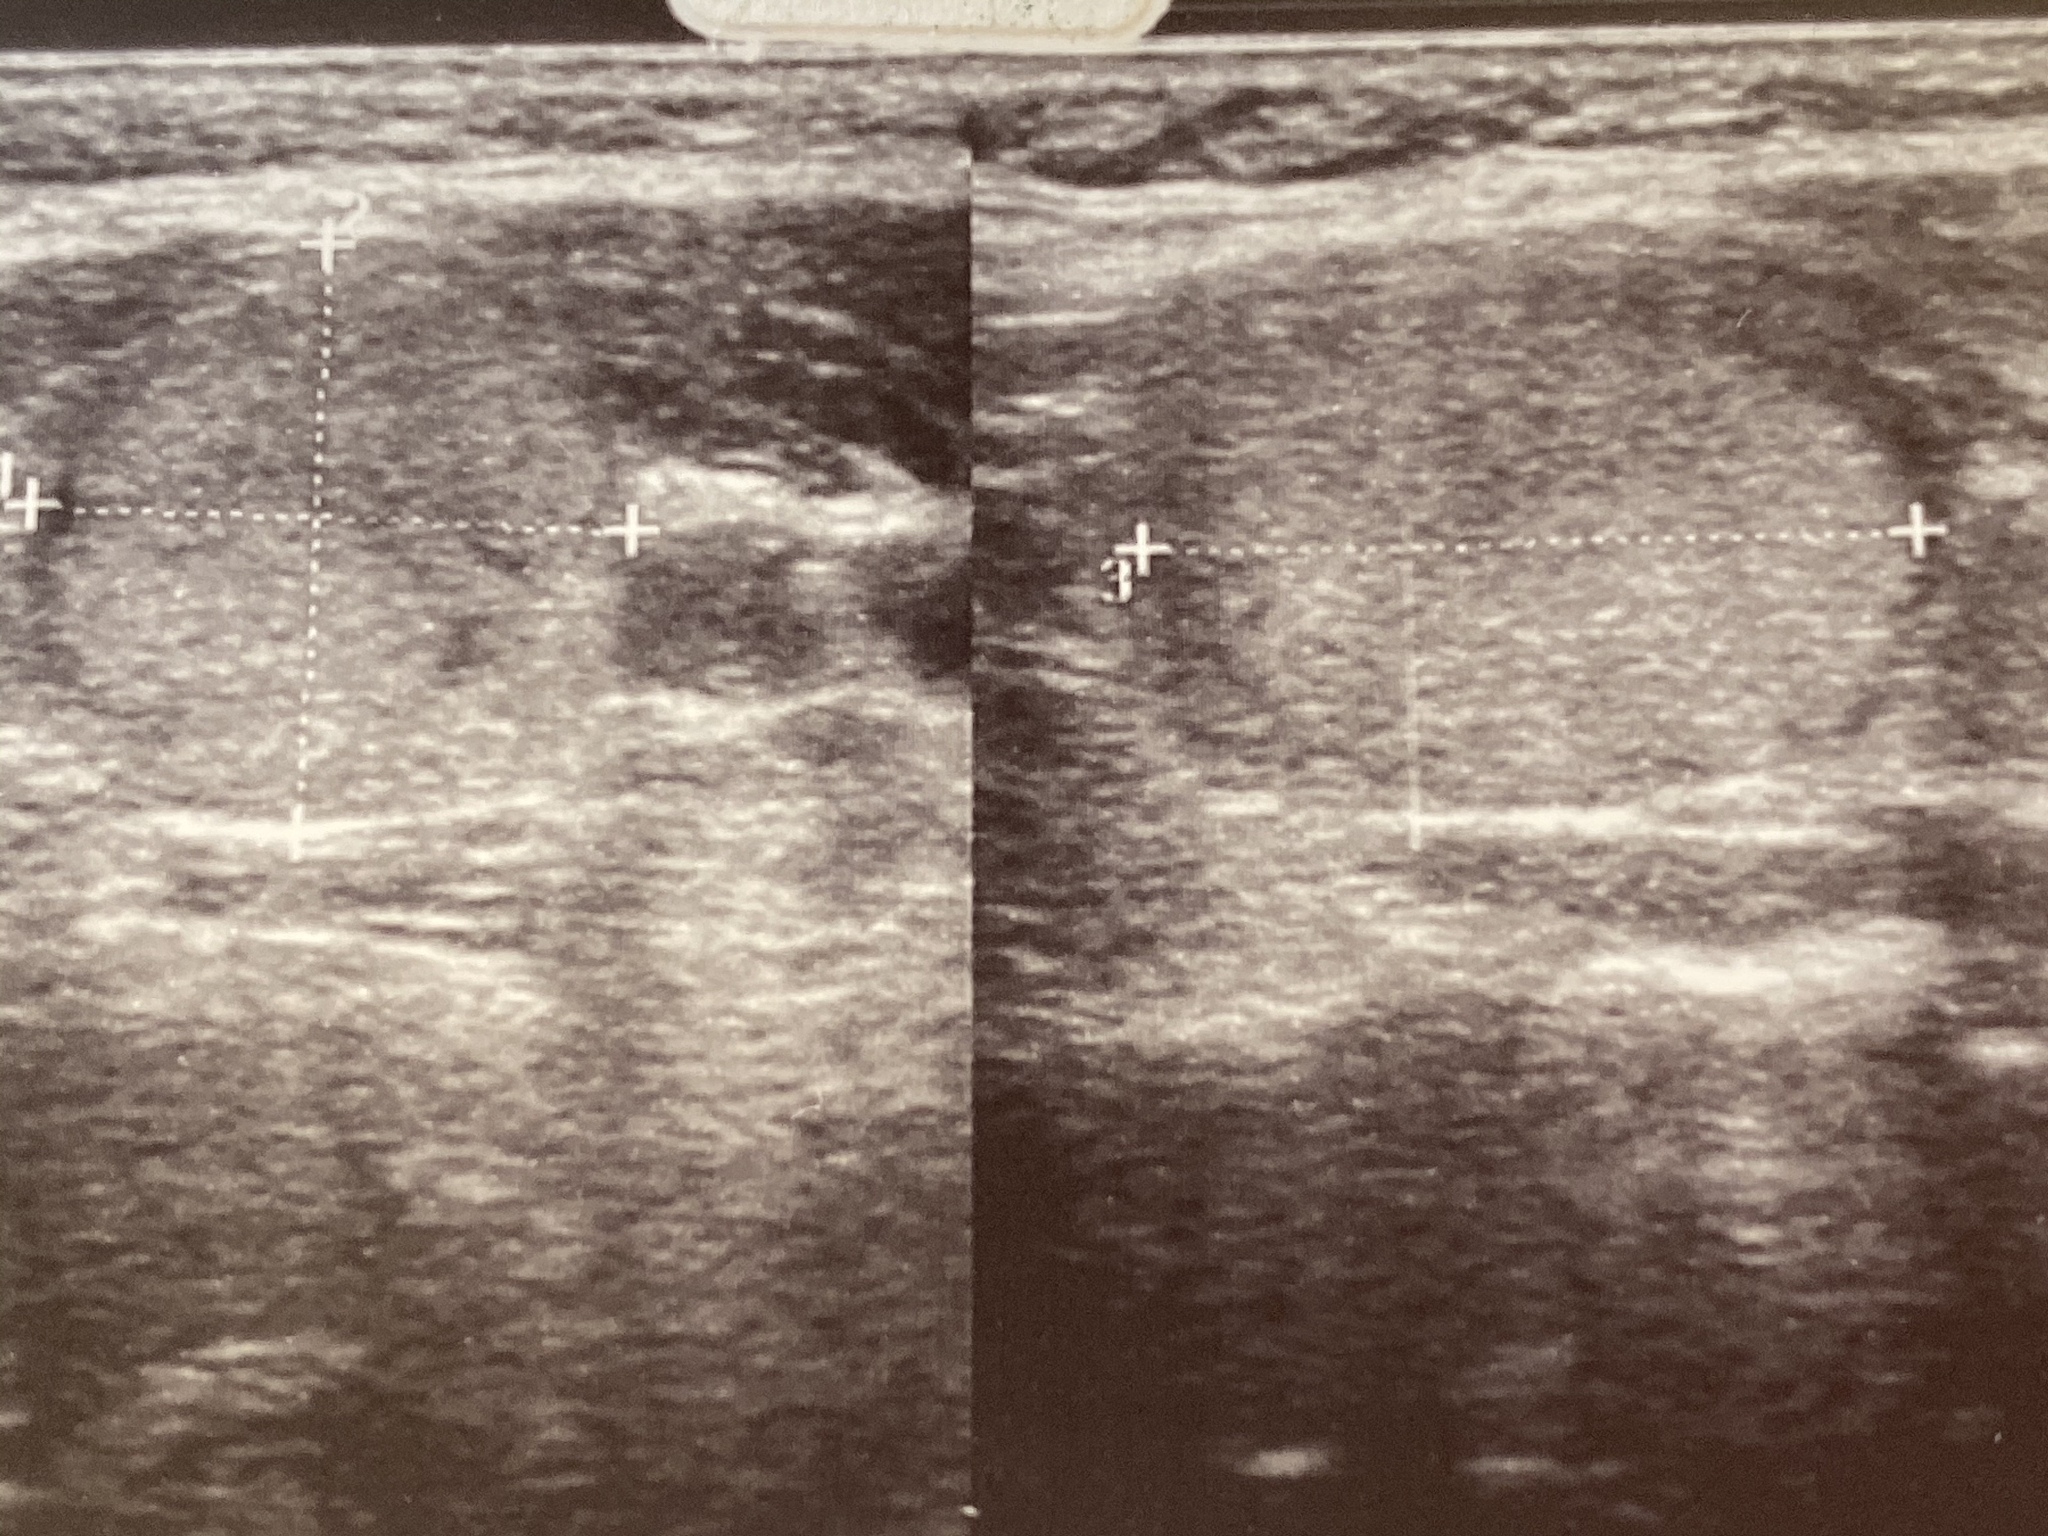

诊断甲状腺癌需要进行以下检查:

• 甲状腺超声: 观察甲状腺的大小、形态、内部结构,判断是否有结节。* 甲状腺功能检查: 检测甲状腺激素水平,判断甲状腺功能是否正常。* 甲状腺穿刺活检: 在超声引导下,用细针抽取甲状腺组织进行病理学检查,确定肿瘤的良恶性。